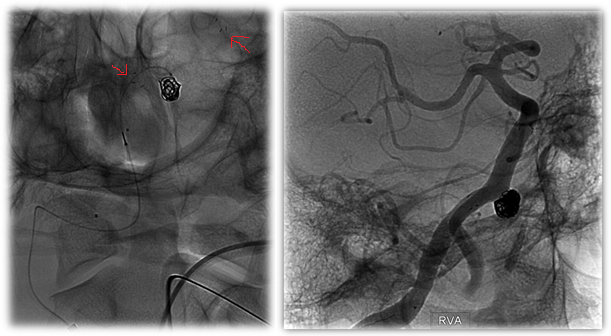

![]() Figure 2: Intraprocedural Images of First Atlas Case. Note the red arrows indicating the radiopaque markers on either end of the stent. |